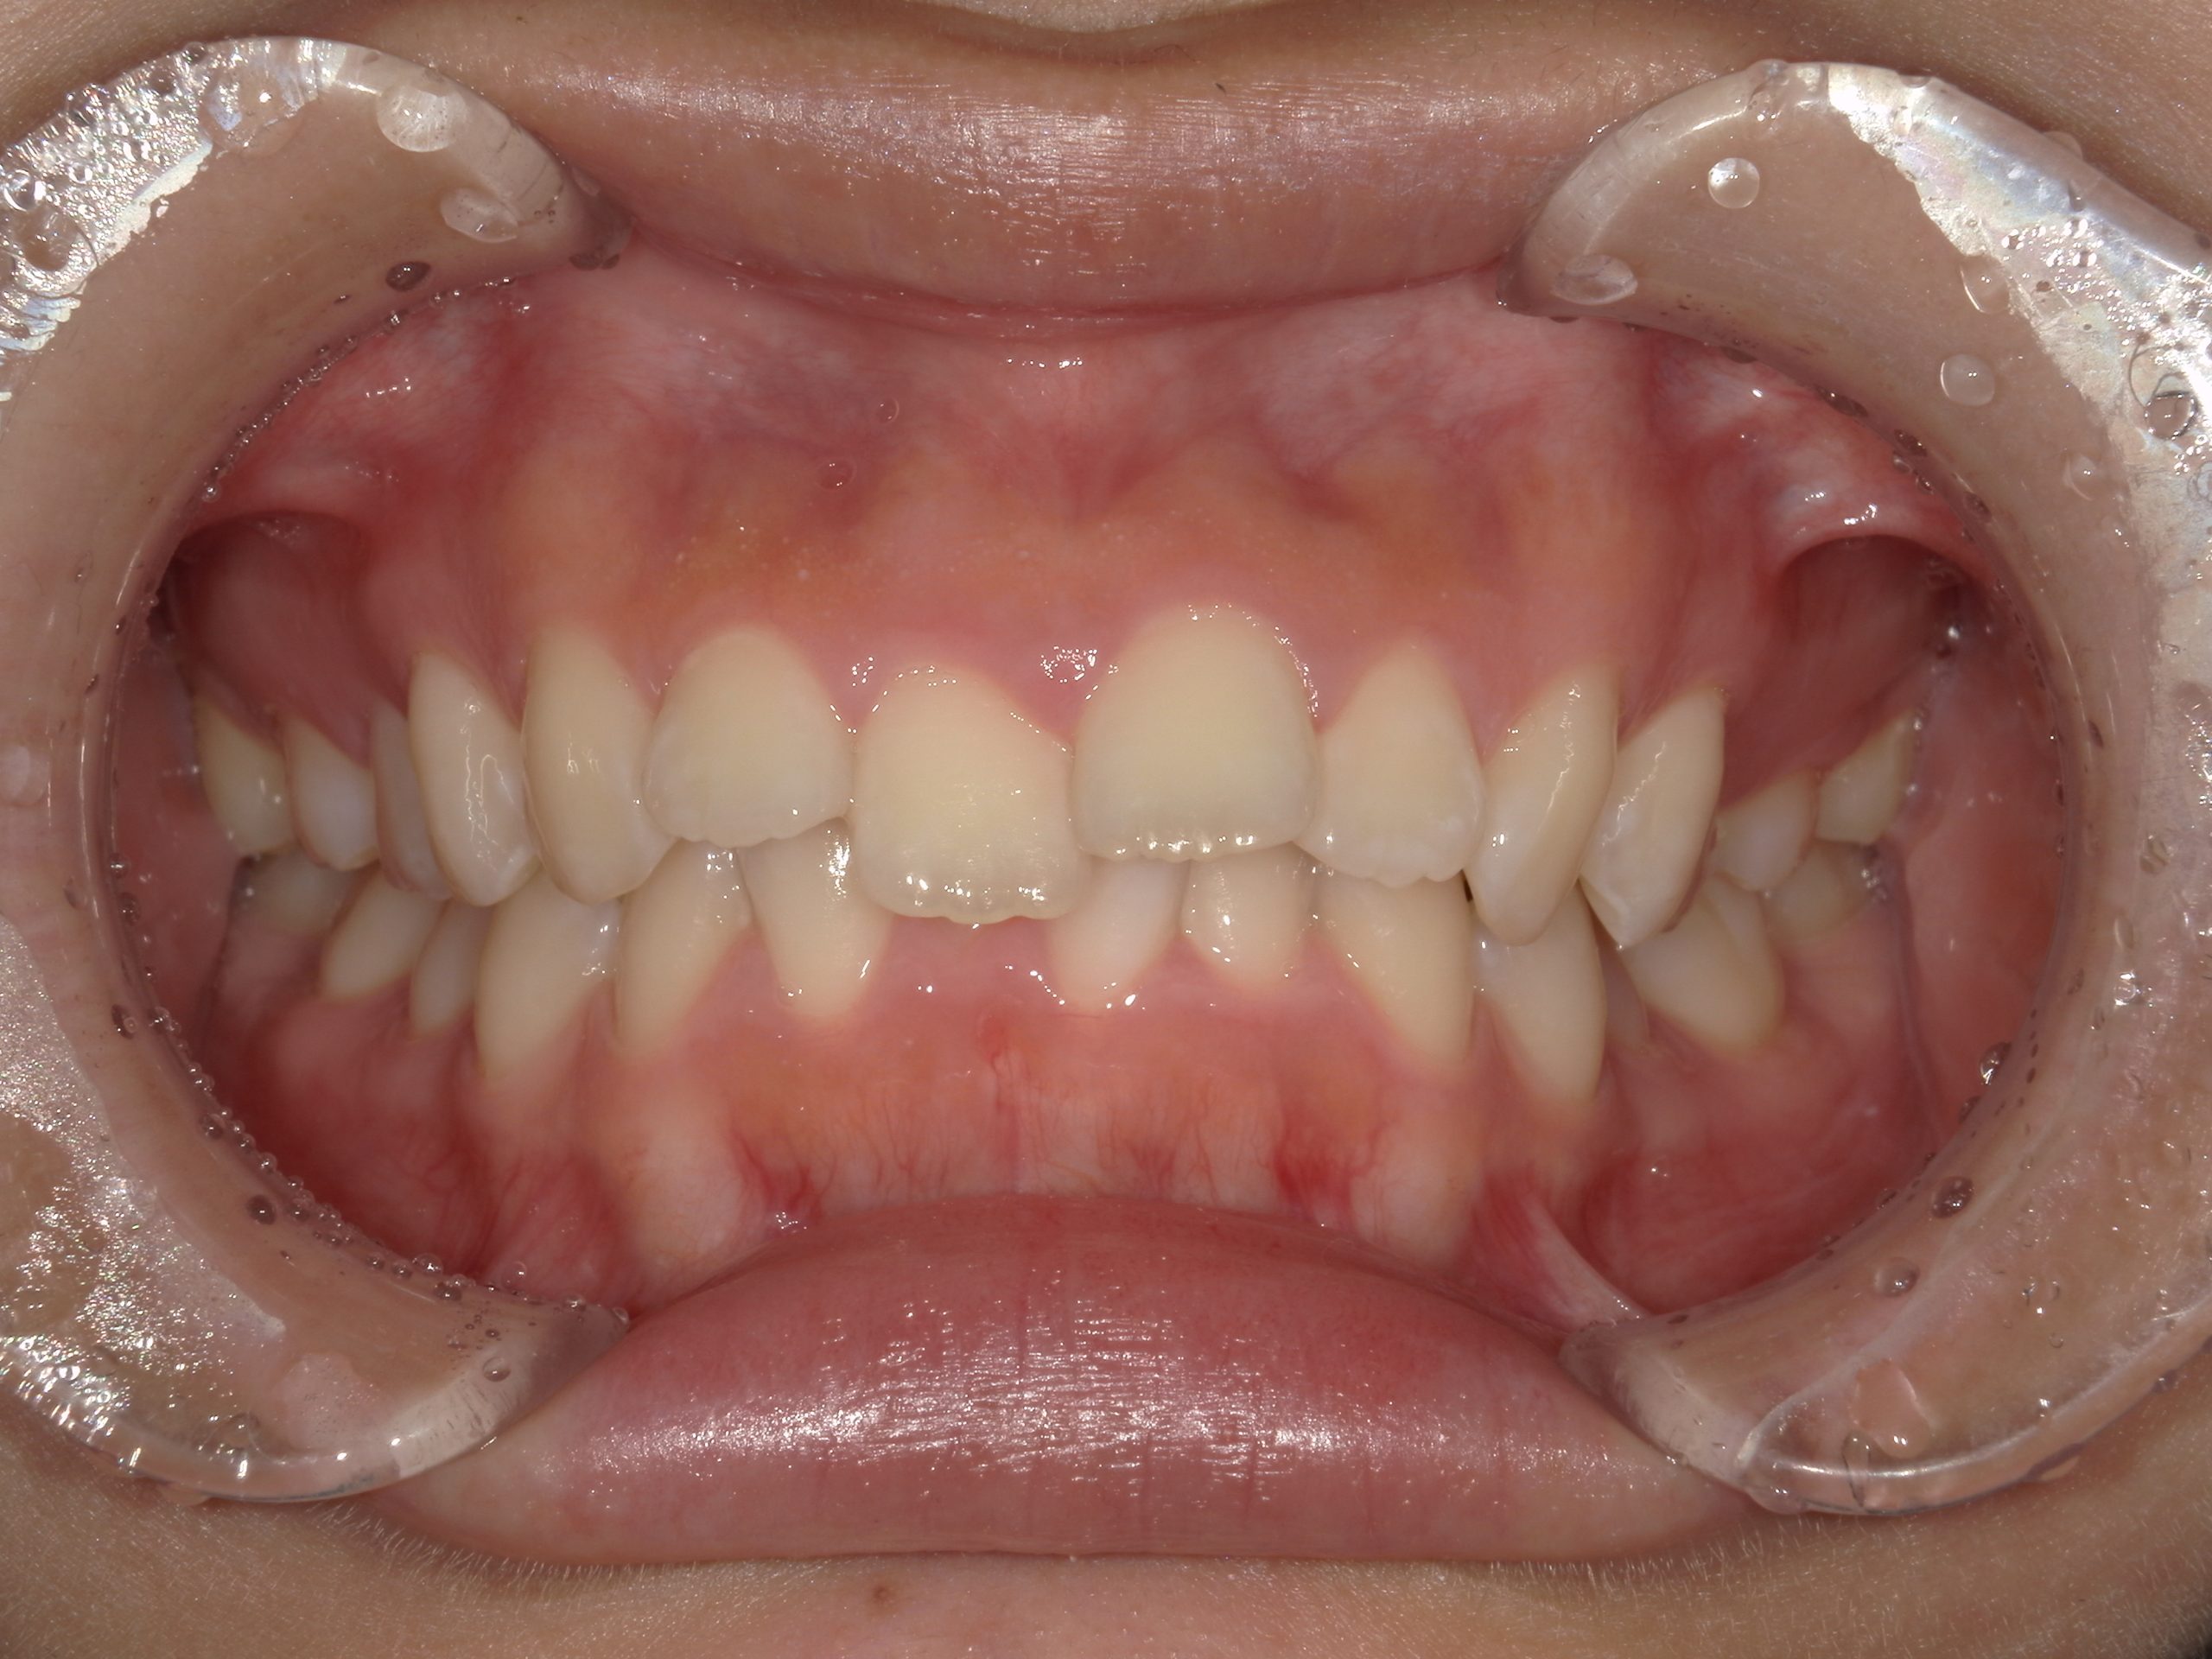

前歯のガタガタ(交叉咬合)と左上奥歯の鋏状咬合を小臼歯を抜歯して改善した症例